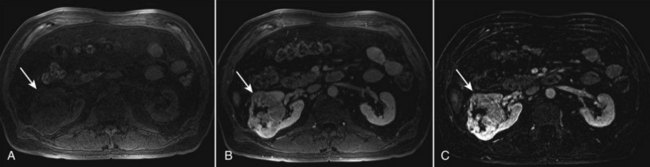

Magnetic resonance imaging (MRI) is the alternate standard imaging modality for the characterization of a renal mass (Pretorius et al, 2000; Zhang et al, 2004; Bassignani, 2006). A basic consideration in the evaluation of a renal mass is that for such a mass to be considered malignant it must enhance with the intravenous administration of contrast material. Such enhancement can now be determined equally well by magnetic resonance angiography with intravenous gadolinium-labeled diethylenetriaminepentaacetic acid, although the assessment is qualitative rather than quantitative. On T1-weighted scans before and after administration of gadolinium, enhancement (vascularity) of the mass is detected (Fig. 49–4). This technique is most helpful in patients for whom iodinated contrast medium is contraindicated because of severe allergy. One concern with MRI with gadolinium is the uncommon but potentially serious complication of nephrogenic systemic fibrosis (NSF), which is more common in patients with renal insufficiency (Bach and Zhang, 2008). Current recommendations are to avoid MRI, particularly serial studies, in this population whenever possible, and to dialyze patients after the study if severe chronic kidney disease (CKD) is present. MRI was previously the imaging procedure of choice in patients with CKD and a renal mass. Now many radiologists prefer CT with intravenous contrast and careful periprocedural hydration, but decision making must be individualized. Contrast-enhanced ultrasonography using microbubbles has also shown promise for the safe characterization and assessment of enhancement of renal masses and may play an important role in patients with CKD in the future (Simmons et al, 2007).

Figure 49–4 Unenhanced and contrast-enhanced MR images of renal cell carcinoma (arrows). A, Unenhanced fat-saturated T1-weighted volume-interpolated breath-hold examination (VIBE) image. B, Contrast-enhanced VIBE image. C, Subtraction image generated by electronically subtracting image A from image B shows a large enhancing mass in the lateral anterior right kidney that is partially exophytic and extends to the central sinus. Although a subjective assessment of enhancement is often possible after contrast administration (B), any signal intensity remaining on the subtraction image (C) represents enhancement after contrast administration.

(Courtesy of Dr. Brian Herts, Cleveland, OH.)